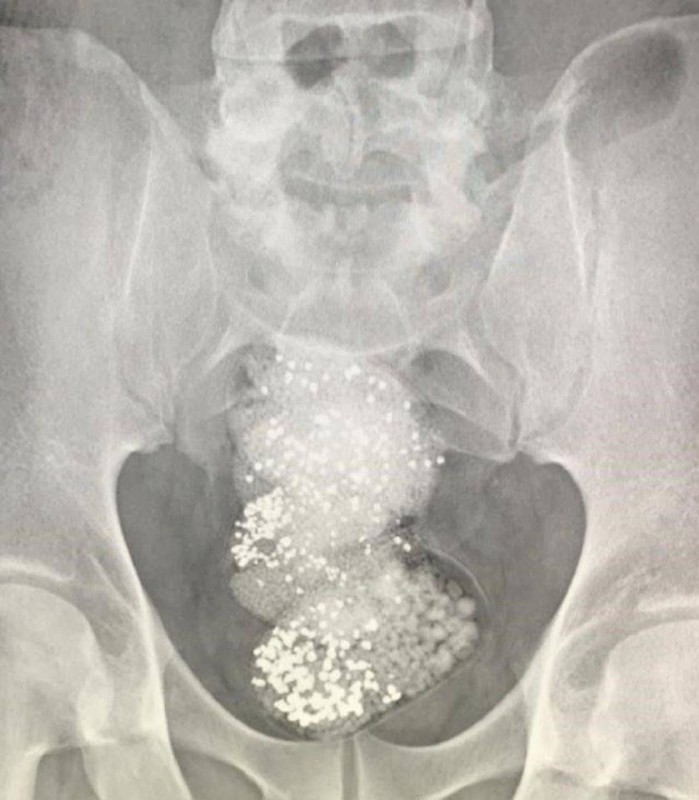

وأضافت الهيئة في بيانها، أنه بعد عرض المسافر على جهاز كشف الأحشاء من قبل جمارك الشارقة تبين قيامه بإخفاء 3 قطع بلاستيكية في أحشائه تحتوي على 297 غراماً من مادة الألماس الخام تبلغ قيمتها نحو 90 ألف دولار أمريكي، حيث تم التحقيق معه ومصادرة الألماس المضبوط وإحالته إلى الجهات المختصة في الدولة لاتخاذ الإجراءات اللازمة.